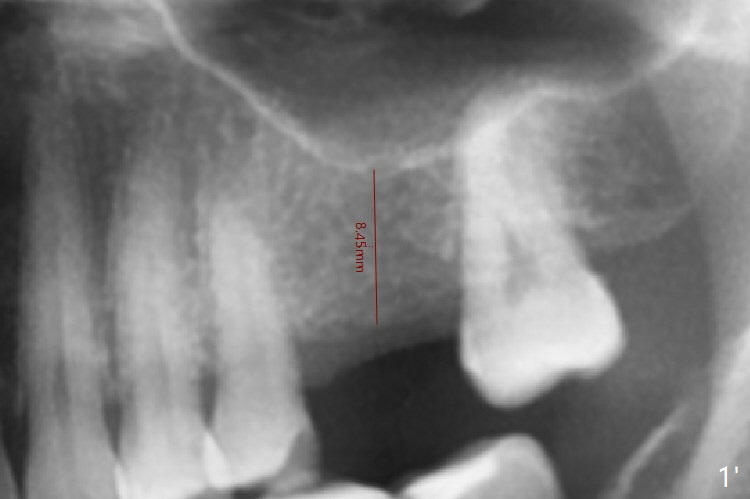

A 49-year-old woman is afraid of dentistry. To reduce anxiety, guided surgery is planned for #30 first (Fig.1). The bone height at #14 is 8.45 mm (Fig.1').